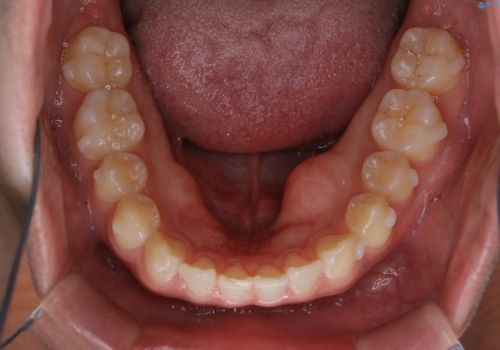

- 上のすきっ歯が気になるとご相談にいらした方です。上下顎ともにスペースがあったため、インビザラインFULLにて見た目と噛み合わせの改善も同時に行いました。

元々は上前歯のみの部分矯正をご希望されていましたが、下の歯もスペースがあり、噛み合わせ的にも上のみの部分治療は難しいことをお話ししました。前歯のみの部分矯正を行った場合、前歯の隙間だけが閉じて奥歯が噛めなくなってしまう場合もあります。インビザラインFULLにて治療することで、噛み合わせと見た目を同時に改善させることができ、大変喜んでいただけました。